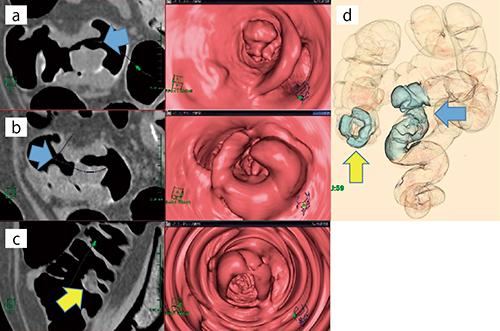

図1は,70歳,女性,便潜血陽性の二次精査として施行した症例である。肛門より29.3cmのS状結腸に,CT値32.3HU,長軸径53.6mmの壁肥厚による強い狭窄が認められる。VEでは肛門側(図1 a),口腔側(図1 b)両方から全周性壁肥厚病変の観察が可能である。さらに,狭窄部より口腔側の観察では,肛門より194cmの上行結腸バウヒン弁付近に壁の肥厚が確認できる(図1 c)。高度の狭窄病変の口腔側にある別の病変もfly throughにて容易に観察できた症例である。

図1 仮想内視鏡画像:VE

a:VE,肛門側から(←)

b:VE,口腔側から(カメラ反転→)

c:VE,上行結腸の壁肥厚(→)

d:VDCBE